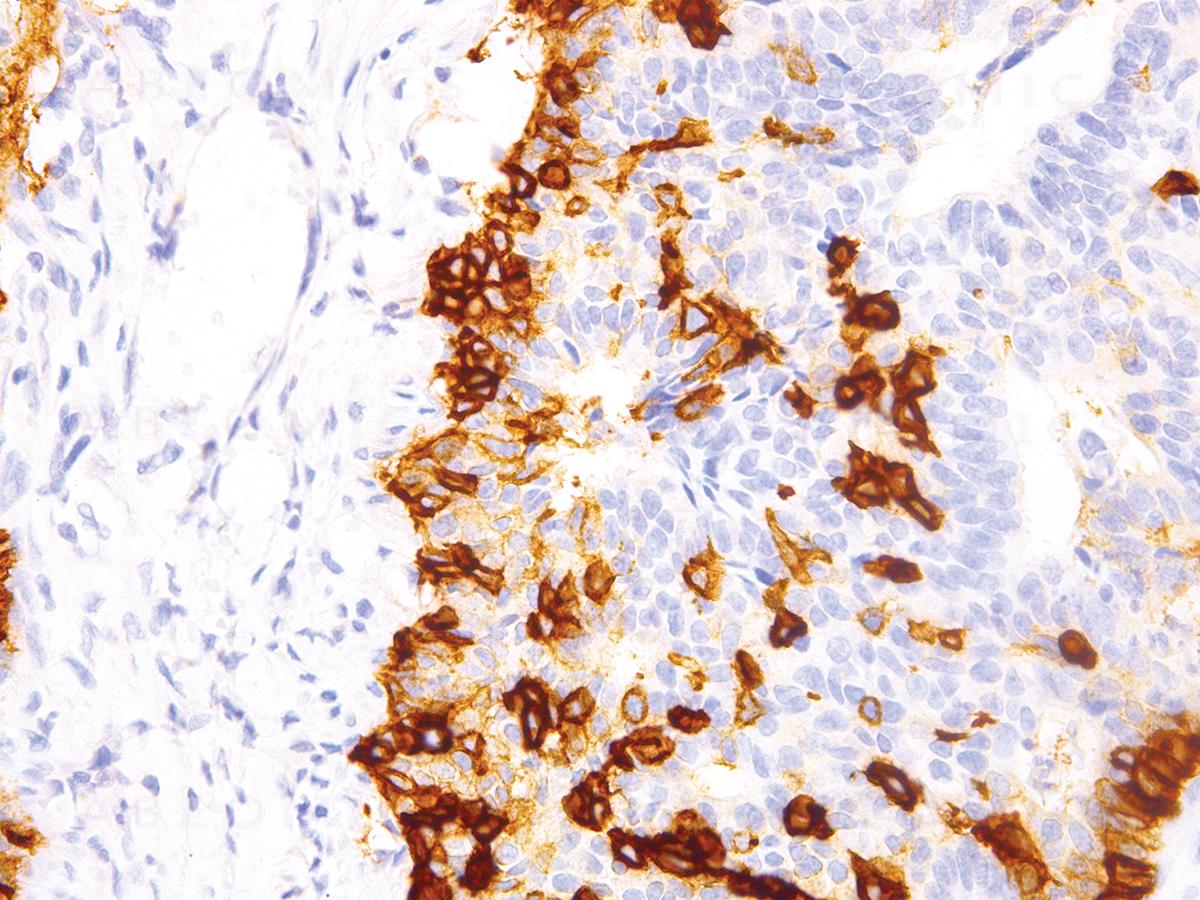

Figure 1: Immunohistochemical analysis of Nerve Growth Factor Receptor (NGFR) (Clone: IHC637) on Cervix

"Nerve Growth Factor Receptor (NGFR), also known as p75, P-75NTR or CD271, is a neurotrophin receptor belonging to the tumor necrosis factor receptor family. NGFR is expressed mainly in Schwann cells and neurons, as well as a number of other non-neuronal cell types, and functions during central and peripheral nervous system development to regulate neuronal growth, migration, differentiation, and cell death. Nerve Growth Factor Receptor is also expressed in melanocytes, melanomas, neuroblastomas, pheochromocytomas, neurofibromas, neurotized nevi (type C melanocytes), and other neural crest cell or tumor derivatives."